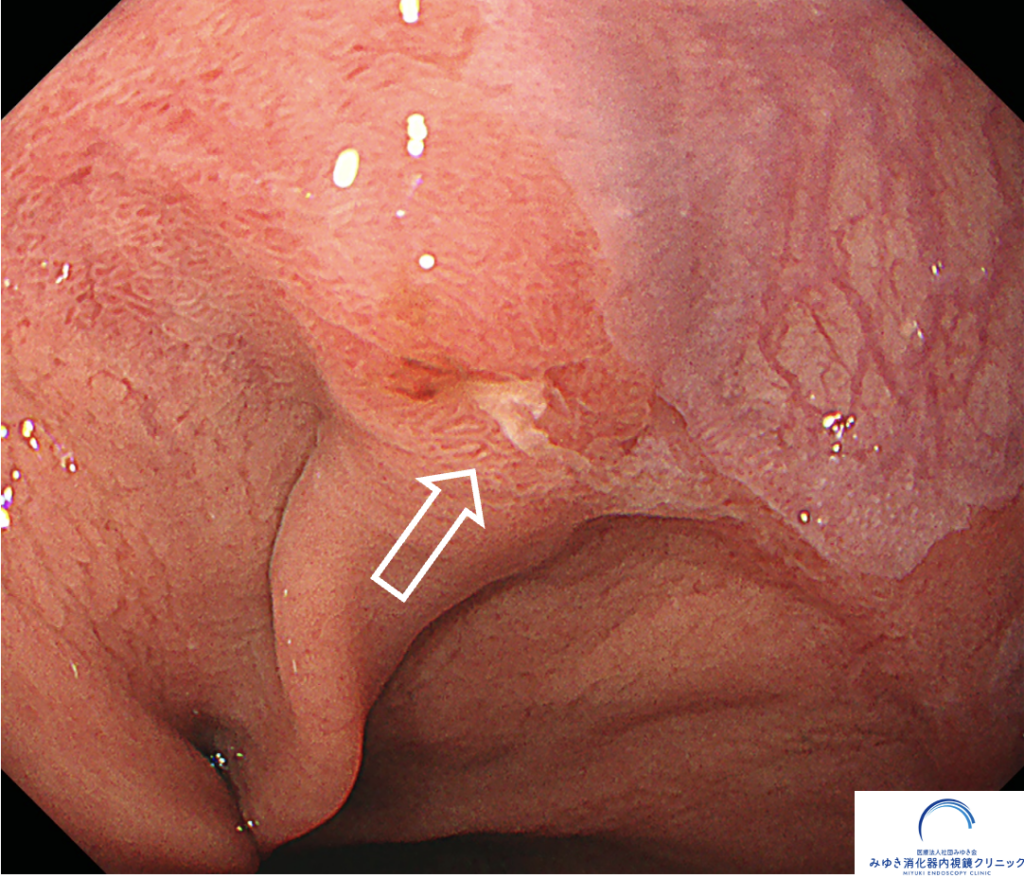

ある検査の際、バレット食道の部分にごく小さな「へこみ(陥凹)」と軽い出血が見つかりました。

NBI観察